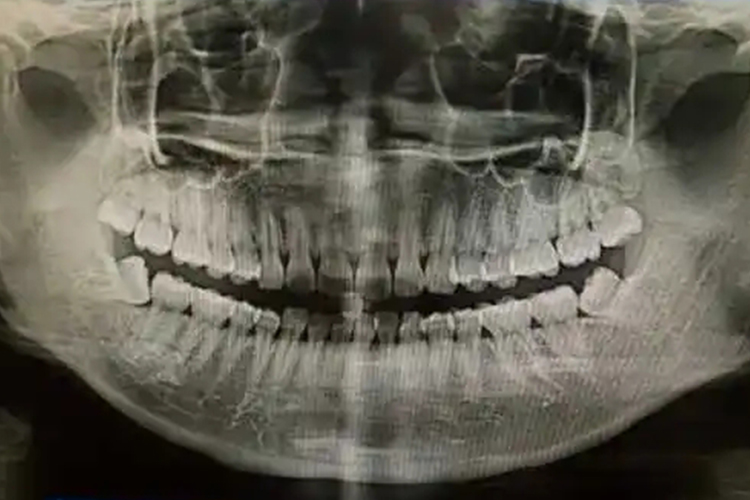

如恒牙总数少于28颗,可能存在先天缺失牙畸形;如恒牙总数大于32颗,则存在额外牙。

正常情况下,恒牙共28-32个,上、下颌的左右侧各7-8个,名称从中线起向两旁,分别为中切牙、侧切牙、尖牙、第一前磨牙、第二前磨牙、第一磨牙、第二磨牙、第三磨牙。部分人群的上、下颌左右可不存在第8颗恒牙,即没有第三磨牙生长,也属于正常现象。

32颗牙齿中,上、下颌左右侧的第三磨牙俗称智齿,部分患者的第三磨牙可出现阻生齿,导致牙齿咬合异常,必要时需及时拔除,避免对其他牙齿产生不良影响。若成年人的恒牙数量大于32颗,则存在额外牙,若恒牙数量不足28颗,则可能存在先天缺失牙畸形。